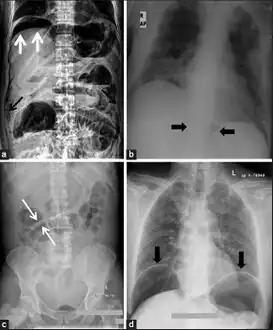

-

a) X-ray of abdomen, showing subdiaphragmatic free air, air outlining the properitoneal fat stripe black arrows b) Cupola sign arrowheads c) Rigler's sign d) chest radiograph showing free air under the diaphragms -

a.b)Pneumoperitoneum developed three days following percutaneous radiologic gastrostomy -

Another pneumoperitoneum on chest X-ray. -

Pneumoperitoneum seen on X-ray with the patient lying on his left side. -